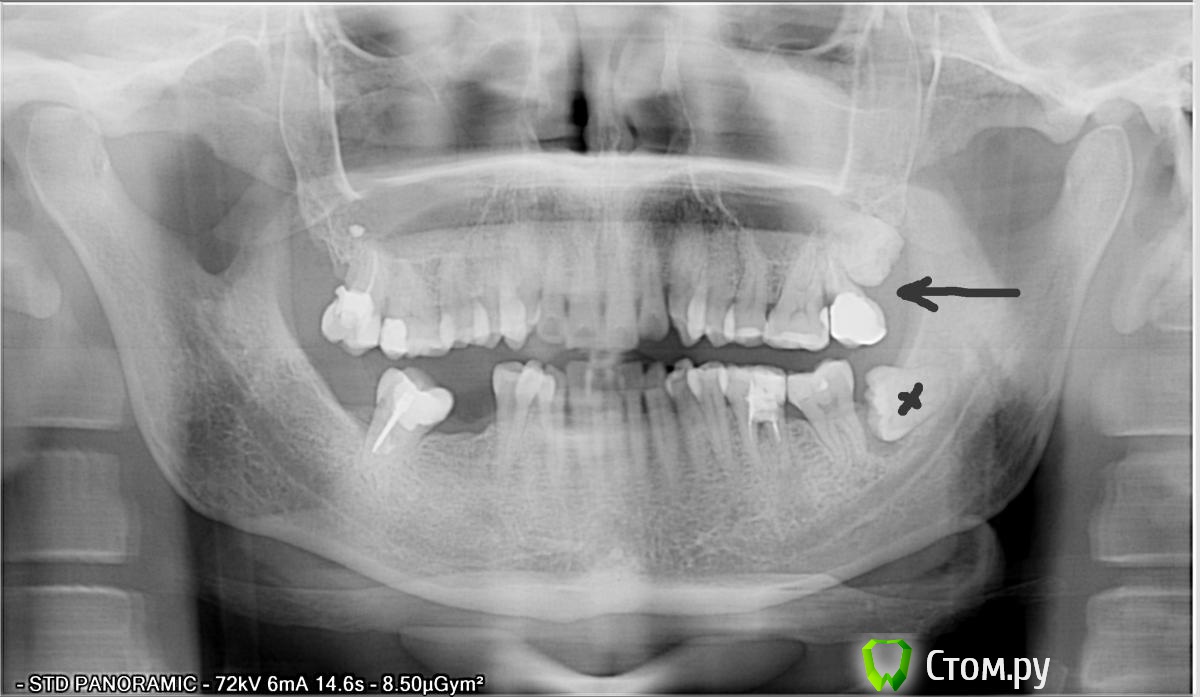

aldenis Опубликовано 13 марта, 2014 Поделиться Опубликовано 13 марта, 2014 Здравствуйте,Болят верхние зубы в районе 7-го зуба, при накусывании и от холодного/горячего. Предполагаю, что надо удалять, 7-й и рядом 8-й, и что-то делать с 6-м - лечить или удалять. Прикладываю снимок, но он сделан 2 года назад, когда удаляли нижний зуб мудрости. Город Москва, к кому можно обратиться, и сколько примерно готовить денег? Заранее спасибо. Ссылка на комментарий

Mane Опубликовано 14 марта, 2014 Поделиться Опубликовано 14 марта, 2014 7-й и 8-й слева вверхупо снимку точно удалять Ссылка на комментарий

aldenis Опубликовано 2 апреля, 2014 Автор Поделиться Опубликовано 2 апреля, 2014 Вслед за хирургом посмотрел и терапевт, и тоже сказал - удалять. В связи с этим прошу мнения стоматологов этого форума, можно ли вылечить такой зуб. 6-й сверху, на снимке крайний слева. 7 и 8 отсутствуют. Хирург и терапевт сказали, нужно удалять, т.к. корень сгнил, мягкий. При осмотре ткнули туда инструментом, боль прострелила мозг И просто болит, и от холодного горячего. Сверху зуб на вид целый, кроме корня. Есть ли какие-то способы сохранить часть зуба?Заранее спасибо Ссылка на комментарий